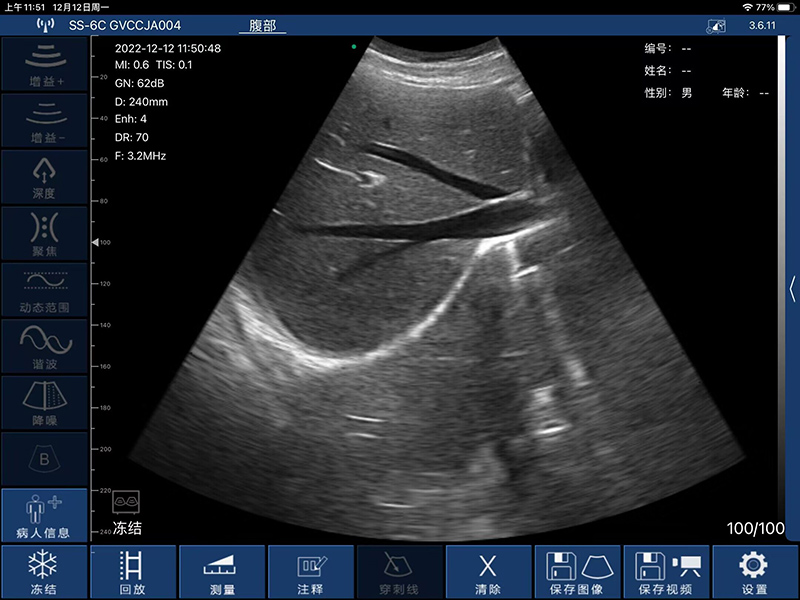

- 扫描深度:90/160/240/305mm,可调

- 显示模式:B、B/M、Color、PW、PDI